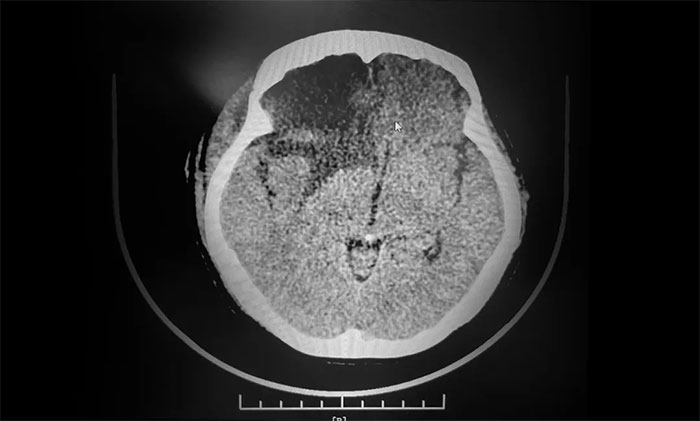

▲ 术后影像,肿瘤已切除

手术顺利完成后,患者生命体征平稳,安返监护病房。留取病理标本送检,确定为脑膜上皮型脑膜瘤(WHO I级),为良性肿瘤。